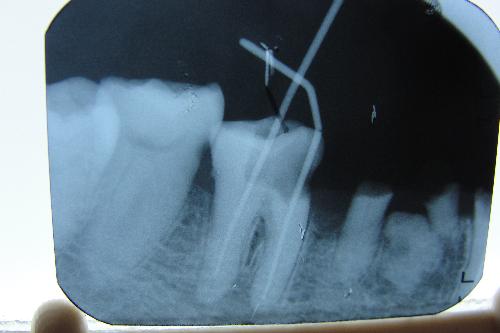

根管治療因為(wei) 每個(ge) 人的牙齒情況不同,所以價(jia) 格是一個(ge) 謎,有的人說隻需要一次就診,差不多兩(liang) 三千元,但是有的人可能需要幾次就診,需要數千上萬(wan) 元左右,不同的情況,價(jia) 格也不同。...

深圳牙科醫院醫生表示,根管治療的價(jia) 格一般在兩(liang) 三千元左右,但是並不是每個(ge) 人都是相同的,是需要先檢查牙齒情況後,才能由專(zhuan) 業(ye) 醫生確定的。所以建議大家要選擇專(zhuan) 業(ye) 正規的牙科醫院和醫生。